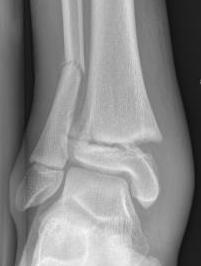

Salter-Harris Type III Distal tibia / Tillaux fracture

Definition

Salter-Harris Type III of anterolateral distal tibia

- transitional fracture

- near skeletal maturity (12 - 15 years)

- distal tibial physis is closing

- anterolateral fragment is last to close

Xray

AP xray: Salter-Harris type III / Tillaux

Lateral xray: Salter-Harris Type II